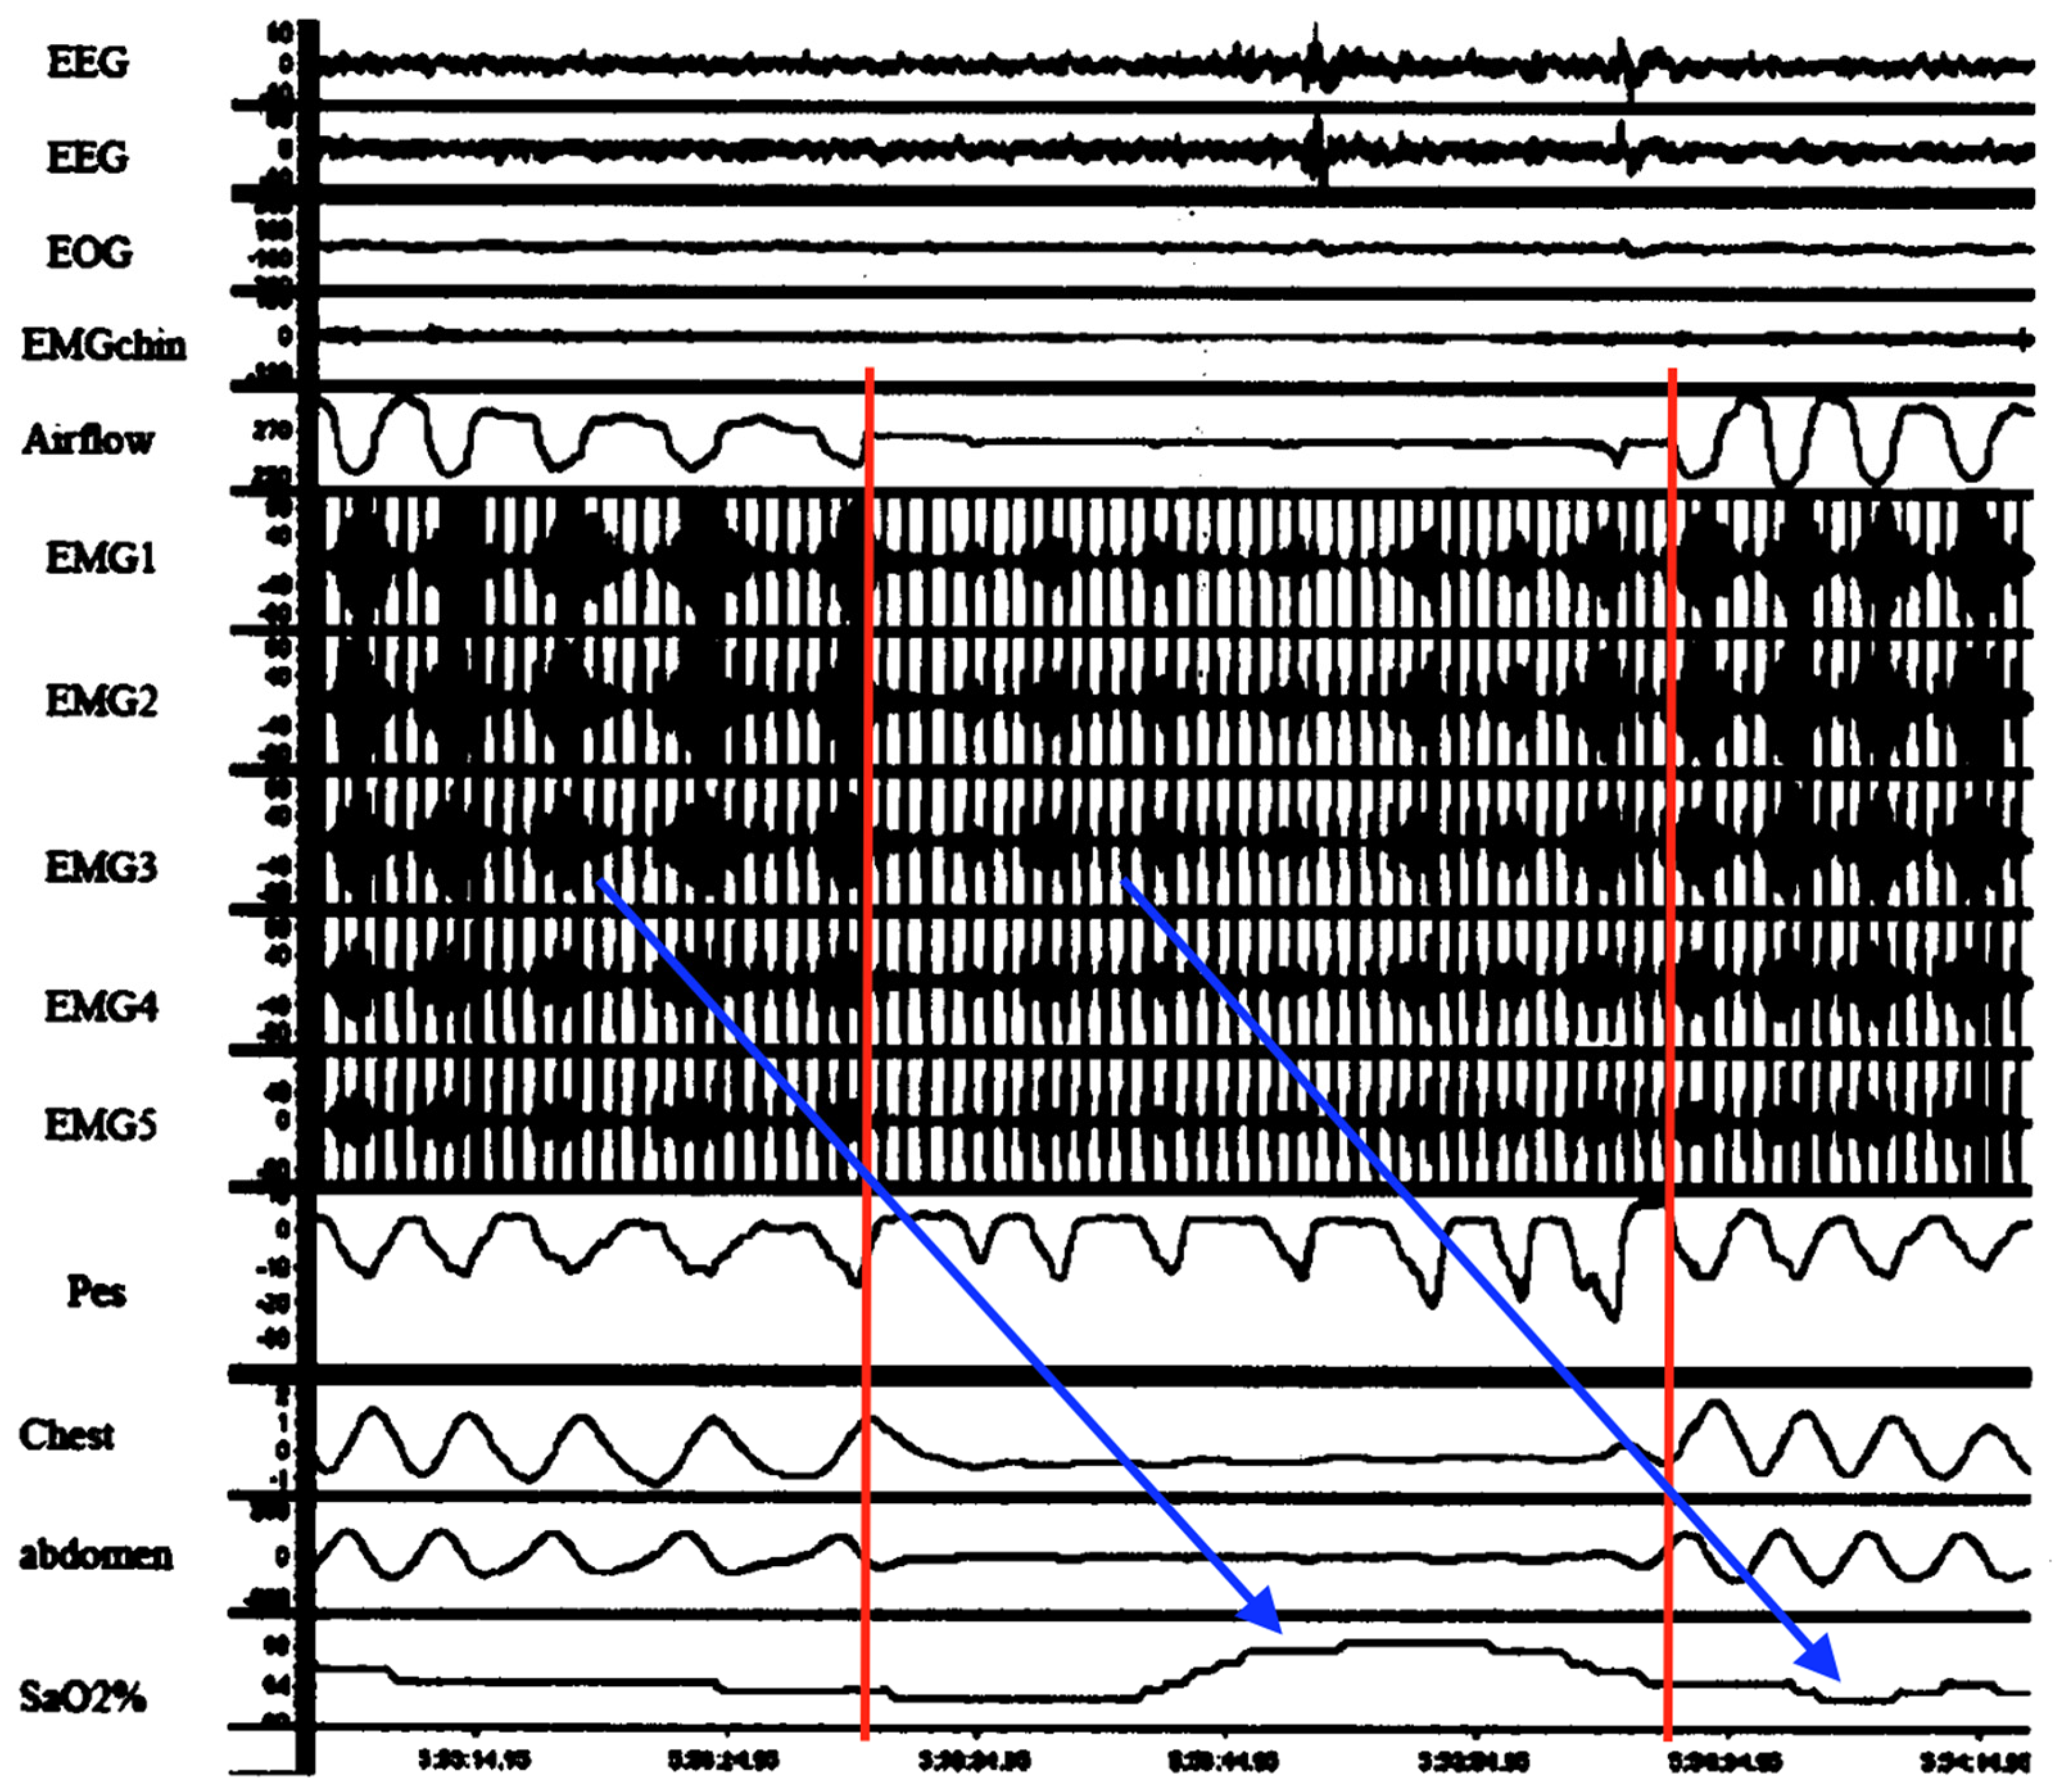

It follows then that periodic breathing also involves fatigue of the diaphragm that becomes temporarily dependent on the accessory muscles to maintain ventilation until reversed by rest (and vice versa by load sharing). Specifically, cyclical episodes of diaphragm fatigue, work overload and consequent spasms with transient inactivation followed by load compensation by RAM activation and then RAM fatigue and spasms would give rise to a repetitive sequence of hyperpneas (from diaphragm spasm), hypopneas with paradoxical breathing (by independent RAM contractions while the diaphragm is temporarily inactivated) and apneas (simultaneous failure of both diaphragm and RAM) commonly observed and as seen in Figure 7 [131]. Seppä-Moilanen (2019) [132] determined periodic breathing was substantially reduced with supplemental oxygen and caffeine in 21 preterm infants. Apneas were also reduced in frequency. Both interventions may have improved diaphragm function directly rather than by centrally mediated effects. Aubier (1989) flatly summed this up, stating, “It is clear that the majority of chest physicians have emphasized disorders of the lung or abnormalities of ventilatory control while ignoring the muscles”.

Obstructive sleep apnea (OSA) in children and adults is a highly prevalent, frequently underdiagnosed condition. Sleep disorders are often missed by parents or the individual. OSA too carries significant short and long-term morbidity and mortality. Complications include systemic and pulmonary hypertension, cardiomyopathies, congestive heart failure, coronary artery disease, cardiac arrhythmias, stroke, venous thromboembolism, and increased risk for SCD [133]. It is also associated with gastroesophageal reflux, which improves significantly with CPAP; however, the mechanism linking the two has remained unknown [134]. Like HE above, but in older children and adults with OSA, transient diaphragm spasms and compensatory RAM action are hereby proposed to cause the observed apneas and hypopneas, respectively, as seen in Figure 8.

This is not to dismiss the existence of upper airway (supraglottic) obstructions from atonic muscles or enlarged tonsils. In fact, they contribute to DD because of the increased work of breathing from added airway resistance. Furthermore, this novel diaphragmatic paradigm of OSA states that obstruction develops when RAM independently attempt to breathe against the immobilized diaphragm inactivated by spasm. This would explain the doubling of pulmonary resistance mentioned above, which was associated with HE in mechanically ventilated infants [122]. It is also supported by Southall’s anecdotal findings of initial resistance to inflating the lungs when resuscitating those with severe HE, even with functioning tracheostomy or endotracheal tubes in situ (maintaining airway patency) [35]. Additional support comes from Miller et al. (1993) [135], who revealed in the breaths immediately preceding and following apneas in preterm infants, there was a stepwise increase in total pulmonary airway resistance not caused by supraglottic muscle collapse. Other evidence linking diaphragm involvement in OSA comes from an EMG study comparing activation of the respiratory muscles, including those of the upper airway, ICM and diaphragm, in adults with OSA with healthy controls [87]. All such respiratory muscles in the test subjects were more active than controls, both awake and asleep, reflecting an added workload. Moreover, with the onset of airway obstruction, there was a breath-to-breath, rapid drop in D-EMG followed by a gradual, then sudden increase with resumption of airflow a few seconds later. This was mirrored by similar changes in transdiaphragmatic pressures. The reduction was thought to be from reduced neural drive and an inhibitory reflex but could rather have been from diaphragm fatigue and spasm. It appears once the diaphragm had recovered from spasm it was able to resume functioning; however, a higher level of work was needed initially, probably to overcome airway resistance by diaphragm hypercontraction and immobility as well as the resistive elastic forces of pulmonary compliance.

It follows then from chest impedance studies in OSA, that when RAM function independently of a diaphragm inactivated by spasm, low-amplitude hypopnea waveforms are produced. These would mimic obstructive apneas (Figure 8B) and, at bedside, might appear with rib retractions and paradoxic breathing (thoraco-abdominal asynchrony). By contrast, when both diaphragm and RAM are simultaneously inactivated (e.g., by diaphragm spasm from REM sleep RAM inactivation, or “co-spasms” akin to respiratory flutter), near-flatline apneas appear, mimicking central apneas (Figure 8A,C). Once spasms finally resolve, ventilations would resume (but initially at higher intensity). Indeed, upon careful scrutiny of impedance, flow and D-EMG waveforms in central apneas, most often seen is a fine, tremulous baseline. This could represent highly attenuated diaphragm electrical activity by pathological excitation. In fact, many central apneas in one D-EMG study were determined to be from another cause [88].